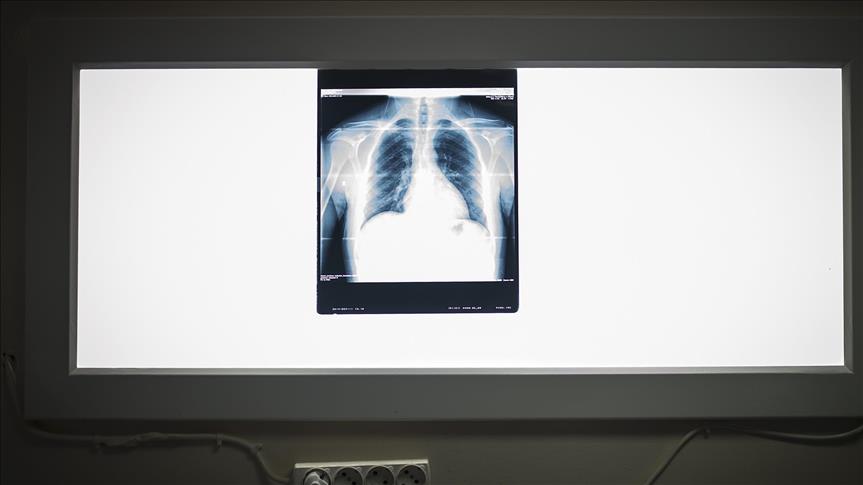

Africa has 28% of the world’s tuberculosis (TB) cases and the highest severe burden relative to population, according to the annual World Health Organization (WHO) Global TB Report released last October. That means 281 cases for every 100,000 people, including 32% of the new HIV-positive cases in Africa in 2014.

The economic burden on the infected as well as African countries’ expenses are often neglected in stories of statistics and numbers. “The monetary impact of TB patients needs to be further explored, as the world often forgets that illness and disease also heavily burden the patient’s ability to provide for their families,” Professor Keertan Dheda, South African National Research Foundation chair in lung infection and immunity, told Anadolu Agency.

As over 318,000 people in South Africa are diagnosed with TB each year, there is a considerable economic impact on the country. The Post-2015 Developmental Agenda report by Dr. Anna Vassal, of the London School of Hygiene and Tropical Medicine states that to reduce TB’s death rate to 90%, $422 million in addition to current spending would be required.